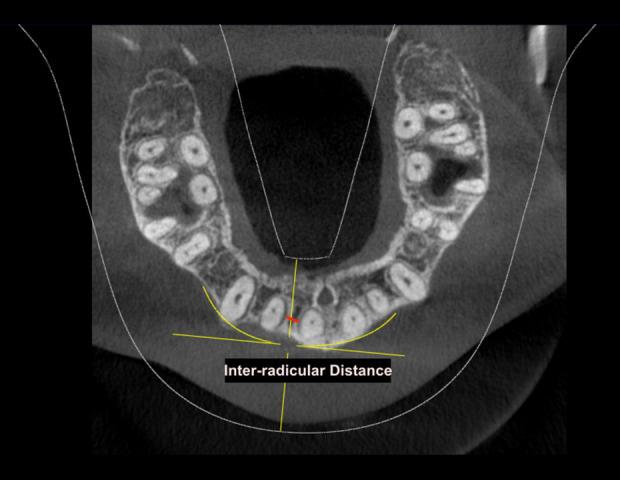

BACKGROUND In this study, we aimed to evaluate orthodontic mini-implant placement in the maxillary anterior alveolar region by cone beam computed tomography (CBCT) in 15 patients at a single center in South India. MATERIAL AND METHODS A total of 15 CBCT scans of orthodontic patients after completion of leveling and aligning stage were included. The thickness of labial alveolar bone, labio-palatal bone, and inter-radicular distance between the maxillary central incisors (U1-U1), maxillary central and lateral incisor (U1-U2), and maxillary lateral incisor and canine (U2-U3) at vertical levels 4 mm, 6 mm, and 8 mm above the interdental cementoenamel junction were measured. Descriptive statistics, ANOVA, and Tukey post hoc tests were done to assess the differences among the groups. An independent t test was done to analyze differences by sex. RESULTS The thickness of cortical bone in the labial region was higher in the U2-U3 site than in the U1-U1 site, at a height of 4 mm. Also, there was a significant difference between 4 mm and 8 mm heights in the U2-U3 region. No significant difference was noted in bone dimensions among men and women and in the labio-palatal bone thickness among the different sites. The inter-radicular distance was the highest between the U2-U3 site, while it was the lowest in the U1-U2 site. CONCLUSIONS The findings from this center showed that when CBCT was used to evaluate orthodontic mini-implant placement in the maxillary anterior alveolar region, the U2-U3 and U1-U1 locations at heights between 6 mm to 8 mm apical to the interdental cementoenamel junction were optimal for placement of the mini-implants.

共纳入 15 名正畸患者的 CBCT 扫描,均已完成整平排齐阶段。测量上颌中切牙(U1-U1)、中切牙和侧切牙(U1-U2)以及侧切牙和尖牙(U2-U3)之间的唇侧牙槽骨、唇腭侧骨和根间距离,在牙间釉牙骨质界上方 4mm、6mm 和 8mm 的垂直高度。采用描述性统计、方差分析和 Tukey 事后检验评估组间差异。采用独立 t 检验分析性别差异。

唇侧皮质骨厚度在 U2-U3 部位高于 U1-U1 部位,在 4mm 高度;U2-U3 部位在 4mm 和 8mm 高度之间存在显著差异。男女之间的骨尺寸无显著差异,不同部位的唇腭侧骨厚度也无显著差异。根间距离在 U2-U3 部位最高,在 U1-U2 部位最低。

本中心的研究结果表明,当使用 CBCT 评估上颌前牙槽嵴区的正畸微型种植体植入时,牙间釉牙骨质界上方 6mm 至 8mm 高度的 U2-U3 和 U1-U1 部位是微型种植体植入的最佳位置。